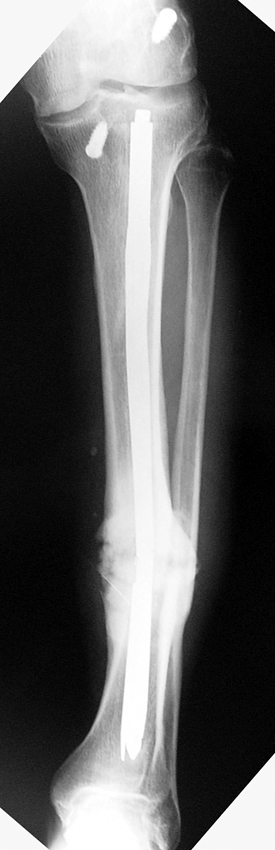

Management of Stiff Hypertrophic Nonunions by Distraction Osteogenesis – A Report of 16 Cases

Tibial nonunion

(JBJS) Nonunion 2006